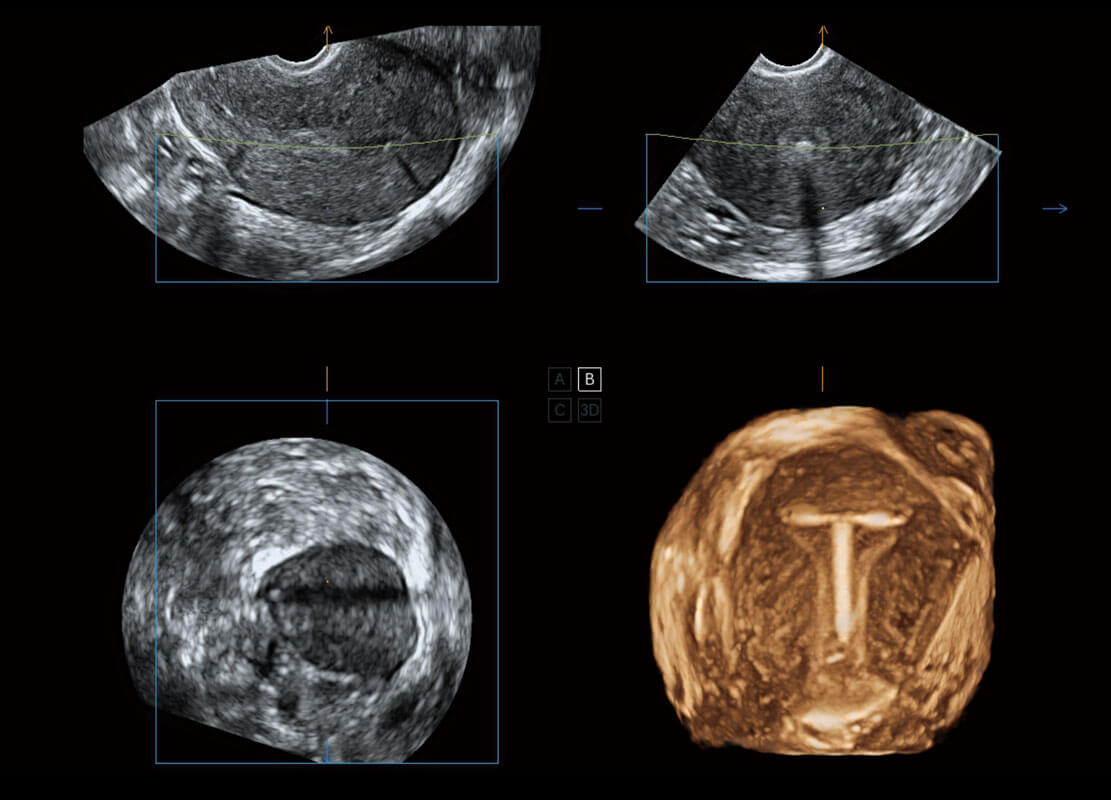

腔内三维-宫内节育器

P60搭载一系列胎儿心脏成像技术,实现精细的胎儿心脏评估。

胎心容积成像